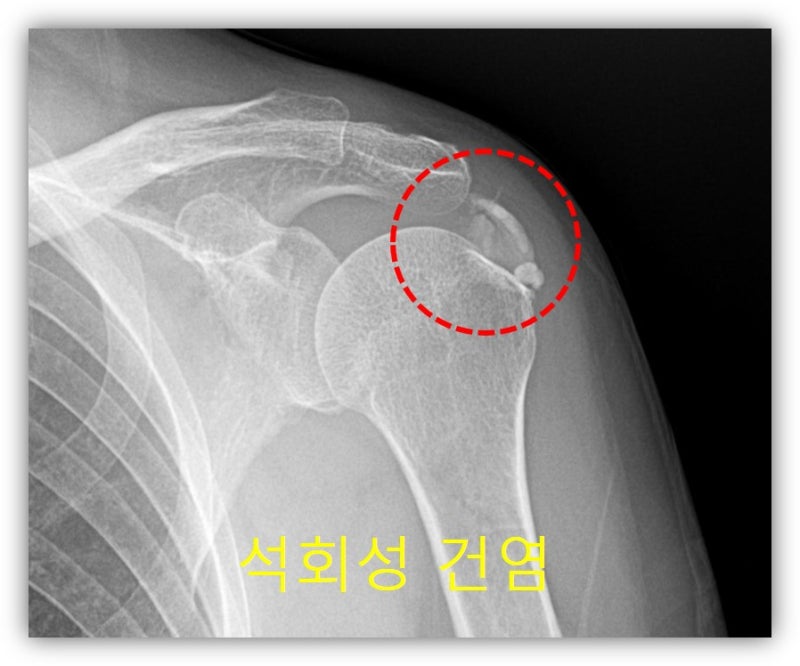

뉴핌스 치료 후 사진과 같이 석회가 많이 제거된 x-ray 를 확인할 수 있습니다. 조금 석회가 남아 있으나 향 후 체외충격파 치료를 추가적으로 시행하면 완전히 제거가 될 것으로 사료됩니다. 환자는 시술 다음날 부터 통증이 거의 없고 팔도 잘 움적여 진다며 환하게 웃으십니다. 석회성 건염 치료는 그냥 통증만 제어한다고 해결되지 않습니다. 석회를 제거해야만 석회성 건염에서 탈출할 수 있습니다. 석회성 건염은 뉴핌스치료가 탁월한 효과를 보입니다. 이제 석회성 건염의 고통에서 수술 없이 완전히 벗어날 수 있습니다.